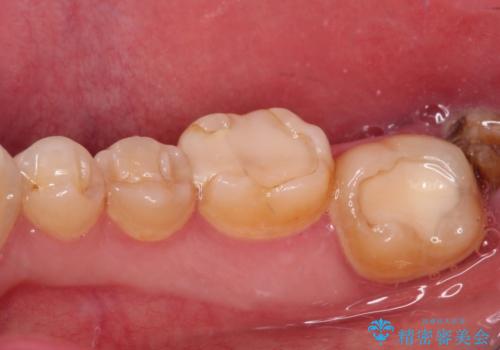

- 左右下顎の奥歯に違和感を感じるとのことで来院された患者様です。

最近ものが挟まりやすくなったり、冷たいものがしみるようになったりと言った症状があり、診査したところ、歯質の欠損や不適修復物などが認められました。

精度の高いセラミックインレーによる修復治療が第一選択となりますが、一方の歯は元々修復物が大きく、咬合力の強い方であったので、セラミッククラウンによる補綴治療を行うこととしました。